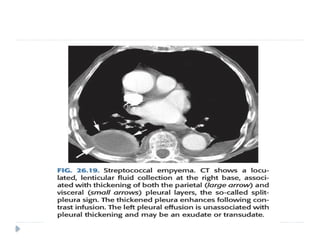

 Empyema:

 Is pus in the pleural cavity.

 The diagnosis is made when the pleural fluid is obviously purulent

 when organisms are identified in the fluid, or when the fluid has an

elevated white blood cell count

 is usually either parapneumonic or postpneumonic.

 Less commonly it may result from transdiaphragmatic extension of

a liver abscess.

 However, CT can help distinguish between pleural

effusion and pleural empyema

 Empyemas usually:

 form an obtuse angle with the chest wall

 unilateral or markedly asymmetric whereas pleural effusions

usually bilateral and similar in size .

 Biconvex , whereas pleural effusions are concave in shape

 Features suggestive of an empyema on CT include:

 Enhancing thickened pleura ( split pleura sign) whereas

pleural effusion has thin imperceptible pleural surfaces

 locules of gas absent unless recent thoracocentesis

 Obvious septations

 Associated consolidation

 Associated adjacent infection (e.g. subdiaphragmatic abscess)